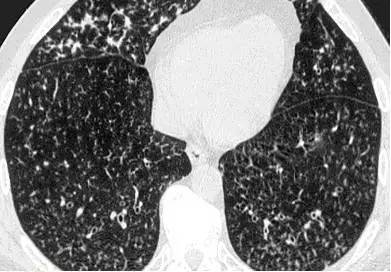

非结核分歧杆菌感染:高分辨率的CT扫描显示右肺多个结节分布于分支线状影周围,支气管扩张壁增厚,黏液嵌塞,支气管肺泡灌洗确诊。